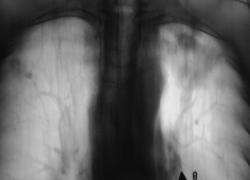

Пациент находится на диспансерном учете в туб. кабинете, по поводу инфильтративного туберкулёза верхней доли левого лёгкого, получает специфическое лечение. Пациент направлен в рентгеновский кабинет для рентгенологического исследования исследования органов грудной полости "в динамике". Проведено стандартное исследование.

Для сравнения приводятся изображения, произведенные чуть больше года тому.